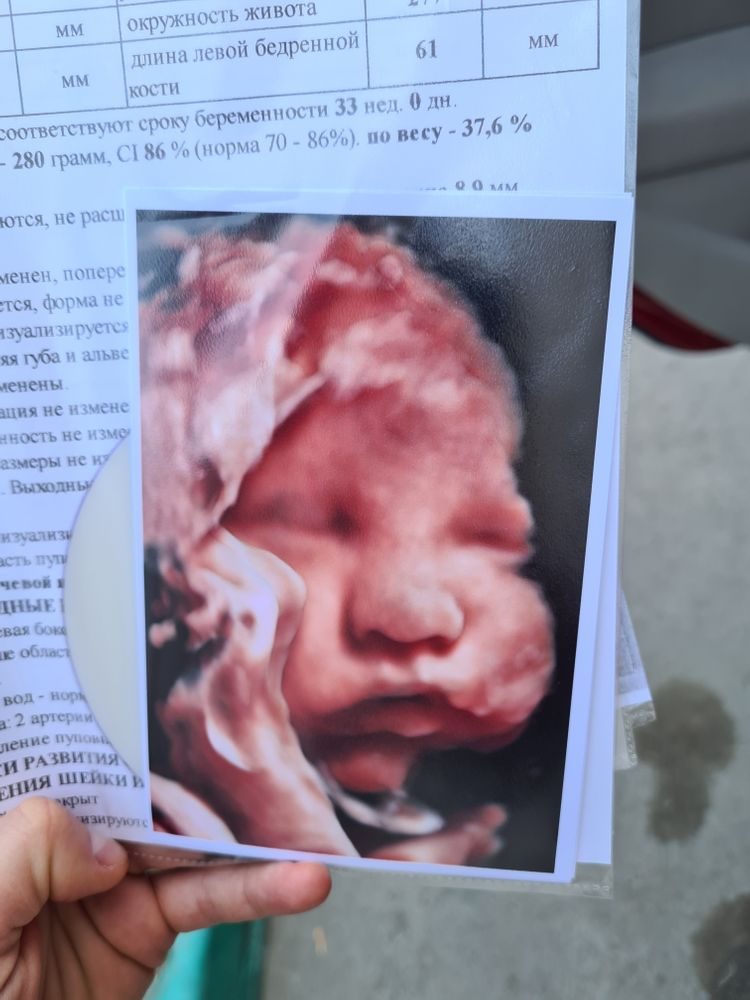

Третий скрининг!❤️ фото удачней, чем на втором☝🏼😝

Малыш у нас прям такой щекастенький, похож наверно больше всего на старшую дочку Лизу.

Сделали фото (удачней чем на втором скрининге в Пеларгосе получилось).

Сладкие шёчки🥰